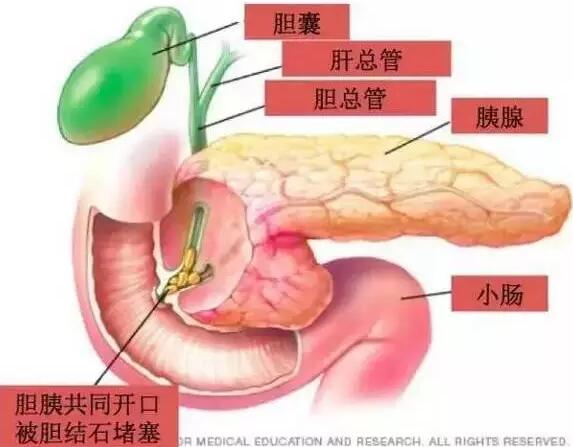

据当时参与抢救的结石科主任介绍,我们这位同事发生急性胰腺炎的罪魁祸首就是那颗小结石,是典型的胆源性胰腺炎。由于结石从胆囊掉出,嵌顿在壶腹部,使胆道内压力剧烈增高,高压的胆汁逆流胰管,造成胰腺腺泡破裂,胰酶进入胰腺间质而发生胰腺炎。如果处理不及时,可发展为重症胰腺炎,死亡率很高。万幸的是该同事的结石自己掉出来了。

在重症胆源性胰腺炎伴有壶腹部嵌顿结石,合并胆道梗阻者,应急诊手术或早期(72小时内)手术,解除胆道梗阻,取出结石,畅通引流,并根据病情需要选择作胆囊切除术。